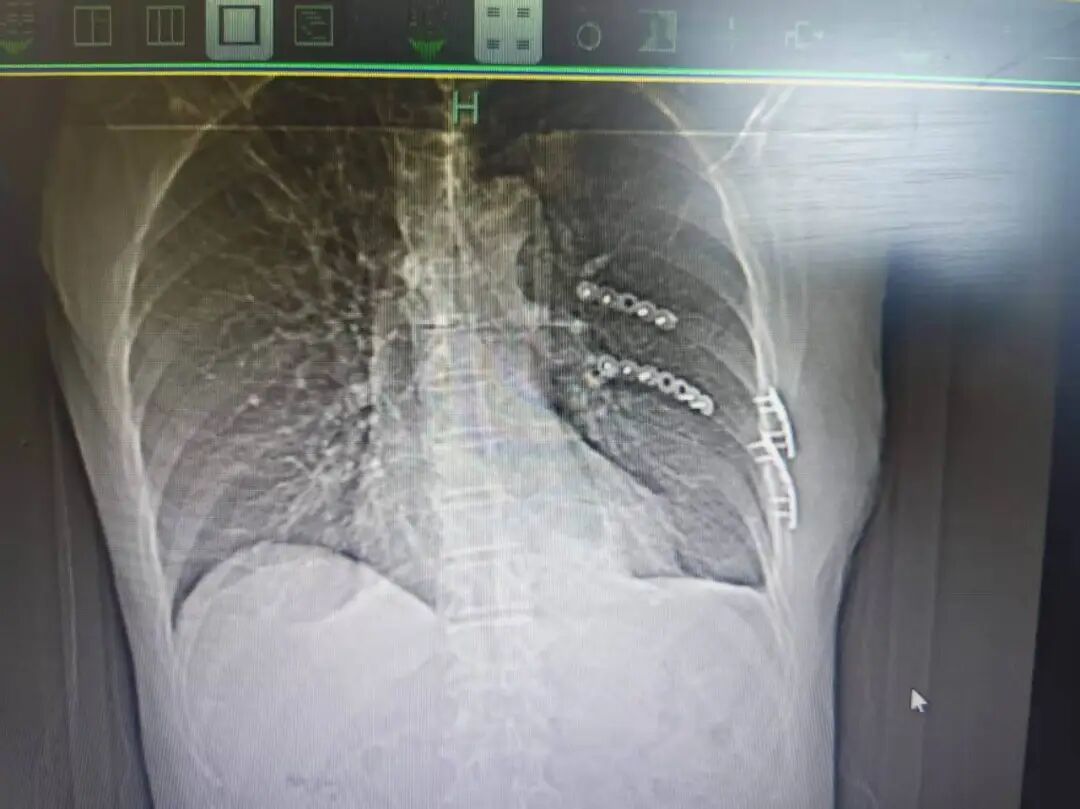

“患者被送到医院时,我们发现他共有13根骨头发生骨折,部分为单根多处断裂且合并左侧气胸。”接诊的杭州市富阳中医骨伤医院胸部创伤组莫军杰副主任医师对此感触很深,多发骨折会破坏胸廓稳定性,对中老年人而言更是“致命危机”:肋骨既是胸廓的保护支架,也是呼吸运动的助力器,一旦多根肋骨发生断裂,患者会本能地不敢深呼吸及咳嗽,这会导致肺部通气不足,痰液无法排出,进而引发肺部感染。

此外,肋骨内侧紧邻心脏和肺脏,移位的骨折断端可能直接戳破肺组织引发气胸、血胸,若不及时处理,可能导致心肺功能衰竭等严重并发症,甚至还会危及生命。

杭州市富阳中医骨伤医院供图

之后,医院迅速启动急救流程,经全面评估,莫军杰医生团队决定为裘叔进行手术,目的是固定骨折的肋骨,并通过引流排出胸腔内积血,解除疼痛并恢复正常呼吸功能。